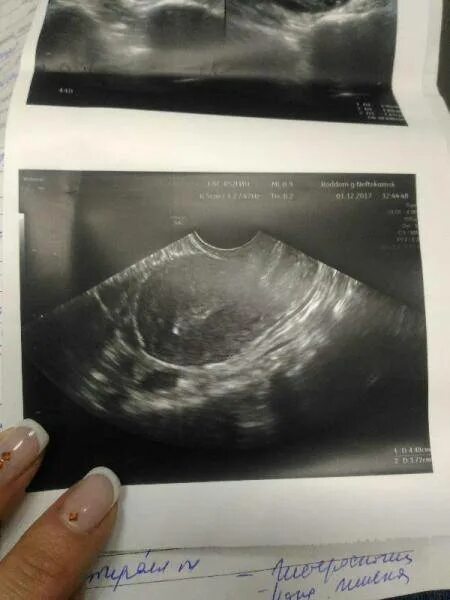

Кальцинат узи